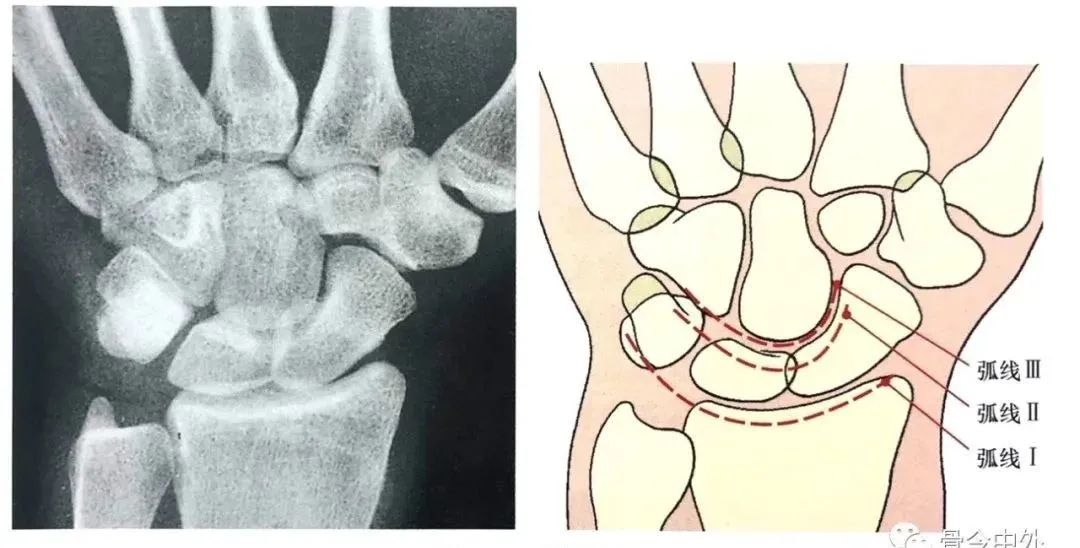

Gilula 提出三个平滑的弧形勾画出近侧列和远侧列腕骨。弧 I 把舟骨、月骨和三角骨近端关节面连在一起;弧 Ⅱ 勾画出上述骨远端凹面;弧 Ⅲ 由头状骨和钩骨远端凸面所形成。

图16腕骨弧。在正常腕关节背掌位X线片上3个平滑的弧线勾画出近侧列和远侧列腕骨。